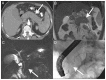

Figure 3:

Diffuse autoimmune pancreatitis. (A) Axial computed tomography (CT) image in the pancreatic parenchymal phase of the typical enlarged and poorly enhanced pancreas in a patient with diffuse autoimmune pancreatitis (arrow). Note the lack of inflammatory change around the organ, which differentiates the disease from acute pancreatitis and necrosis. (B) View of the pancreas using coronal T2-weighted magnetic resonance imaging (MRI) that shows low signal intensity in the pancreas (arrow) because of the diffuse fibrosis in the gland. (C) Coronal magnetic resonance cholangiopancreatography image showing a diffusely irregular pancreatic duct with stenosis distally in the pancreatic head (arrow). (D) Endoscopic retrograde cholangiopancreatography image that confirms the MRI findings, including ductal stenosis (arrow). Images reproduced from reference under Creative Commons licence 2.0 (http://creativecommons.org/licenses/by/2.0/legalcode).